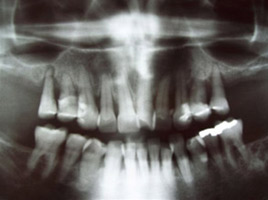

prije

Kirurgija / implantologija